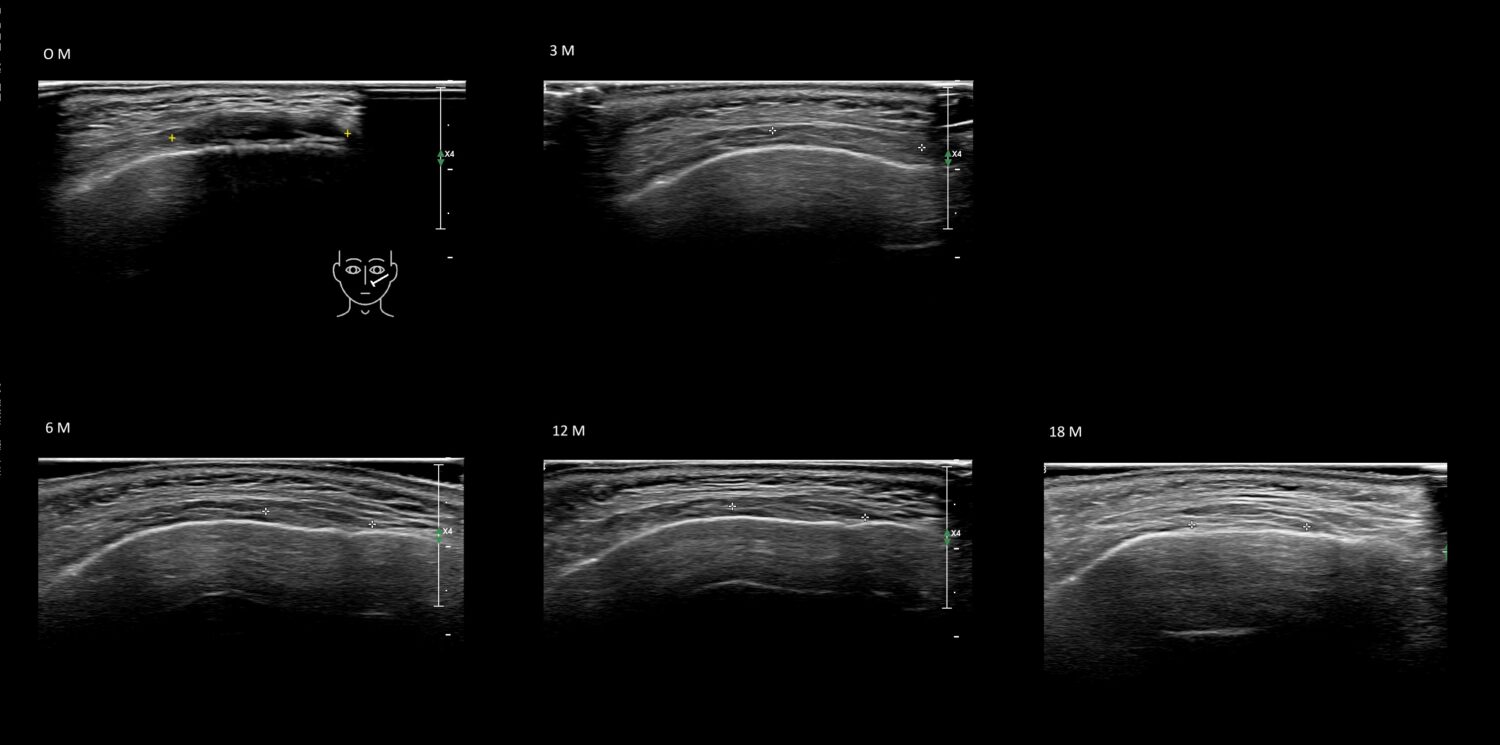

Draw in the image on the right where the fillers are located. To check if your answer is correct, please click on the secondary image.